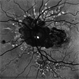

- Angioid Streaks

- 50 YEAR OLD FEMALE WITH NO SYSTEMIC ILLNESS WITH A CLASSICAL PICTURE. VISION REMAINS 6/6. THE FELLOW EYE HAS A SUBFOVEAL SCARRED CHOROIDLA NEOVASCULAR MEMBRANE.